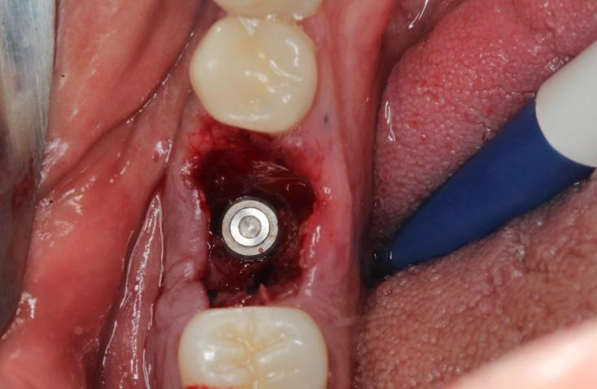

Uma paciente de 62 anos de idade apresentou-se com queixa de odor ruim na região do dente 46, pus, bolsa profunda e sangramento à sondagem. Os exames radiográficos evidenciaram lesão periapical, tratamento endodôntico e uma linha de fratura condenando a sobrevivência do elemento dentário 46. Assim, o elemento foi extraído e foi instalado um implante dentário de conexão interna morse no momento da exodontia. O mesmo foi estabilizado a 20Ncm e o parafuso de cobertura foi instalado. Em seguida, um biomaterial de origem bovina foi compactado no GAP e uma membrana não absorvível foi posicionada protegendo o biomaterial.

Após a análise clínica e tomográfica foi realizado o planejamento do caso: exodontia do dente 46 com a instalação imediata de um implante Cone Morse de corpo cônico (Maestro 4.0 X 9 – Implacil De Bortoli, São Paulo, Brasil), regeneração óssea guiada com biomaterial de origem bovina e colocação de uma barreira regenerativa não absorvível Cytoplast.

Através deste relato de caso observou-se que por meio da avaliação dos exames clínicos e radiográficos de maneira criteriosa pode-se chegar ao diagnóstico definitivo de casos de fratura/trinca radicular, permitindo um planejamento adequado do caso. A realização de exodontia atraumática seguida de implante imediato, possibilitando a preservação da anatomia alveolar e preservando a estrutura óssea, apresenta-se favorável para o paciente, pois reduz o número de intervenções cirúrgicas. Além disso, o uso da técnica de regeneração óssea guiada na Implantodontia, promovendo o preenchimento deGAP nos alvéolos com biomaterial de origem bovina, favorece o aumento ósseo. Por fim, a utilização de uma membrana não absorvível (Cytoplast) intencionalmente exposta ao meio bucal é uma alternativa previsível de tratamento nos casos de preservação alveolar.